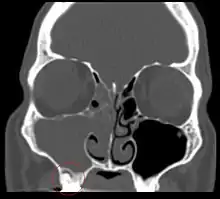

Odontogenic sinusitis

Sinusitis is inflammation of the paranasal air sinuses. Odontogenic sinusitis is an inflammatory condition of the paranasal sinuses that is the result of dental pathology, most often resulting from prior dentoalveolar procedures, infections of maxillary dentition, or maxillary dental trauma.[5] Infections associated with teeth may be responsible for approximately 20% of cases of maxillary sinusitis.[6] The cause of this situation is usually a periapical or periodontal infection of a maxillary posterior tooth, where the inflammatory exudate has eroded through the bone superiorly to drain into the maxillary sinus. Medical management and treatment of the underlying dental pathology remains a critical initial step in the treatment of odontogenic sinusitis, however recent literature suggests that a significant portion of patients may require endoscopic sinus surgery for successful disease resolution.[5] Once an odontogenic infection involves the maxillary sinus, it is possible that it may then spread to the orbit or to the ethmoid sinus.[6]